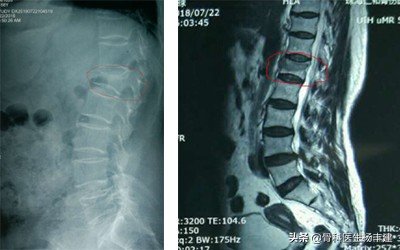

左侧X光可见红圈中的椎体明显变扁了,核磁共振可以看到颜色不一样,说明是新鲜骨折